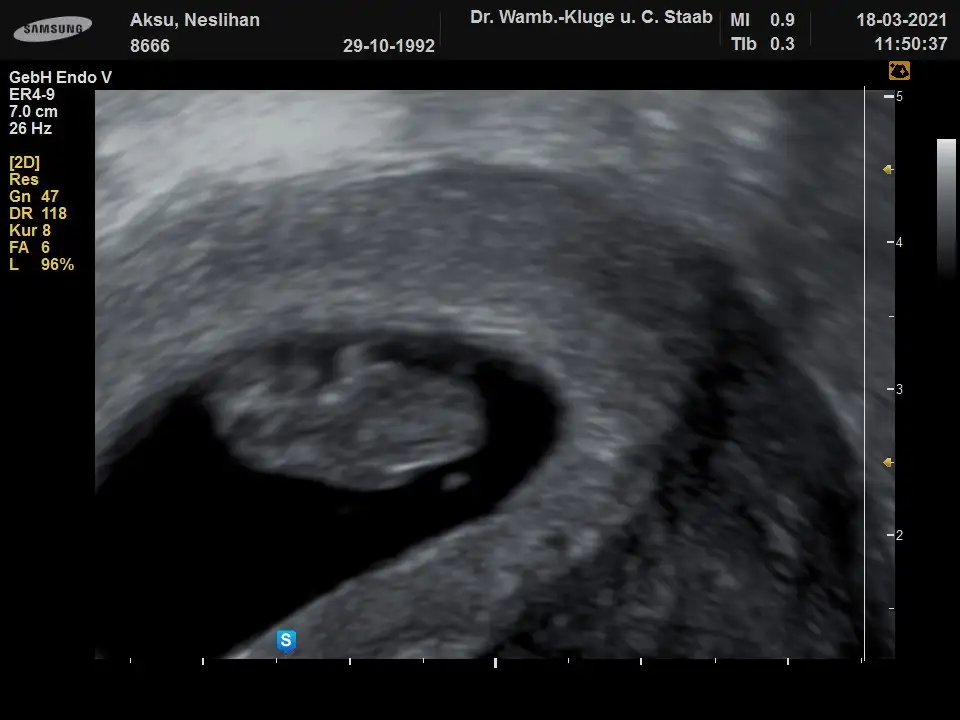

Banada bakabilirmisin lutfen vajinal ult. 9hafta

• 8666_20210318-115037_7.webp

• 8666_20210318-114945_5.webp